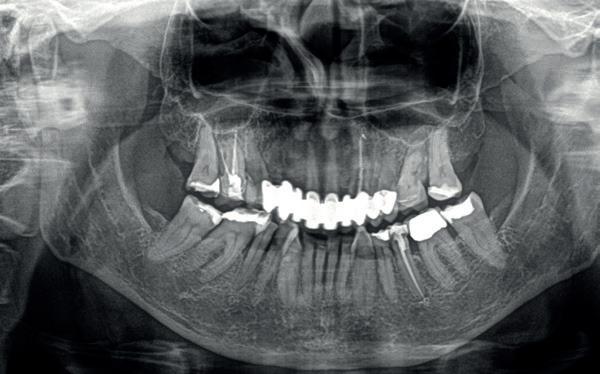

Een patiënt die conventioneel tandheelkundig vrijwel volledig is uitbehandeld, stelt de behandelaar voor complexe keuzes. In dit artikel wordt aan de hand van een uitgebreide casus beschreven hoe diagnostiek, prognosebepaling en interdisciplinair overleg leiden tot een voorspelbaar implantologisch behandeltraject. De casus illustreert hoe een ogenschijnlijk onsamenhangende restauratieve voorgeschiedenis kan uitmonden in een doordacht en succesvol full-arch implantaatgedragen rehabilitatieplan.

Op maandagochtend halfnegen dient zich in mijn agenda een nieuwe patiënt aan, mevrouw G. Ik heb haar nooit eerder gezien en een verwijzend tandarts, stuurt haar in met de vraag of ik met implantaten het eerste kwadrant wil restaureren aangezien daar de brug is losgekomen. Eerder heeft mevrouw G. een uitgebreide informed consent ontvangen met een gezondheidsvragenlijst. Er is verder intensief contact geweest met de verwijzer die ook enkele gemaakte röntgenfoto’s heeft gemaild. Tijdens het eerste onderzoek blijkt dat ze zich goed heeft ingelezen in alle informatie die haar per mail is toegestuurd. De patiënt is 65 jaar oud, spreekt moeilijk Nederlands, echter in het Engels kan ze zich goed verstaanbaar maken. Bij navraag blijkt ze in verschillende landen te hebben gewoond in verband met de werkzaamheden van haar man. Ze is van een economisch hogere sociale klasse en woont nu sinds een jaar of vijf in Nederland. Ze is gezond en slikt geen medicijnen, behalve pijnstillers tegen de pijn in haar gebit.

Door haar vele residenties heeft ze ook veel verschillende tandartsen gehad, verdeeld over een aantal

landen. Ze heeft zich uitgebreid laten behandelen met kroon- en brugwerk. Haar voornaamste klacht is van algemene en esthetische aard: haar gebit doet pijn bij functie en laat esthetisch te wensen over. Haar grootste wens is weer probleemloos te kunnen kauwen met een stevig, pijnvrij en gezond gebit.

Er worden lichtfoto’s gemaakt van het gebit waarop blijkt dat enkel een aantal incisieven in boven- en onderkaak onbehandeld zijn (zie lichtfoto’s bij intake). De residentie lijkt vrijwel geheel gekroond en/ of overbrugd. Er is sprake van gedateerd kroon- en brugwerk waarbij kroonranden met de jaren bloot zijn komen te liggen en er is sprake van secondaire cariës. Daarnaast stel ik een fors verlies van verticale hoogte van de aanwezige processus in alle vier de kwadranten vast. Is hier sprake geweest van een verleden met ernstige parodontitis?

1. Gedateerd kroon- en brugwerk; fors aanhechtingsverlies zijdelingse elementen.

2. Ernstige parodontale afbraak verspreid aanwezig; (sec.)cariës

onder de kronen; grote apicale radiolucentie 16.

3. Paro status bij intake

4. Op basis van de OPG is niet nader te bepalen wat de breedte is van

Op basis van de eerste indruk die ik krijg tijdens het globale klinische onderzoek, wordt een orthopantamogram (zie OPT bij intake) gemaakt. Samen met de meegestuurde röntgenopnames (zie solo’s) wordt eenvoudig vastgesteld dat er sprake is van ernstig botverlies, bijvoorbeeld bij de 16, 17 en de 18 tot 100% verlies aan alveolair bot. De 16 vertoont daarnaast een grote peri-apicale laesie. In het eerste kwadrant lijkt daarom alleen de 12 een goede prognose te hebben. De 12 vormt samen met de 16 een vierdelige brug en deze constructie lijkt dus verloren. Overigens vermoed ik dat de 12 eigenlijk een cuspidaat is en ontbreekt de 12 (agenesie). Daarnaast worden sterk verdiepte ontstoken pockets geconstateerd bij de 16, 17 tot 12 mm en zijn de elementen sterk verhoogd mobiel. De 11 lijkt als enige element van de gehele dentitie niet te zijn behandeld.

In het tweede kwadrant ziet de situatie er in eerste instantie röntgenologisch veel beter uit. Een vierdelige brug rust op twee pijlers: de 24—27. Ook hier is sprake van vermoedelijk agenesie van de 22. Bij nader onderzoek blijkt diepe cariës onder de kroon

de kaak. Voor een accuratere diagnostiek is een CBCT-scan nodig.